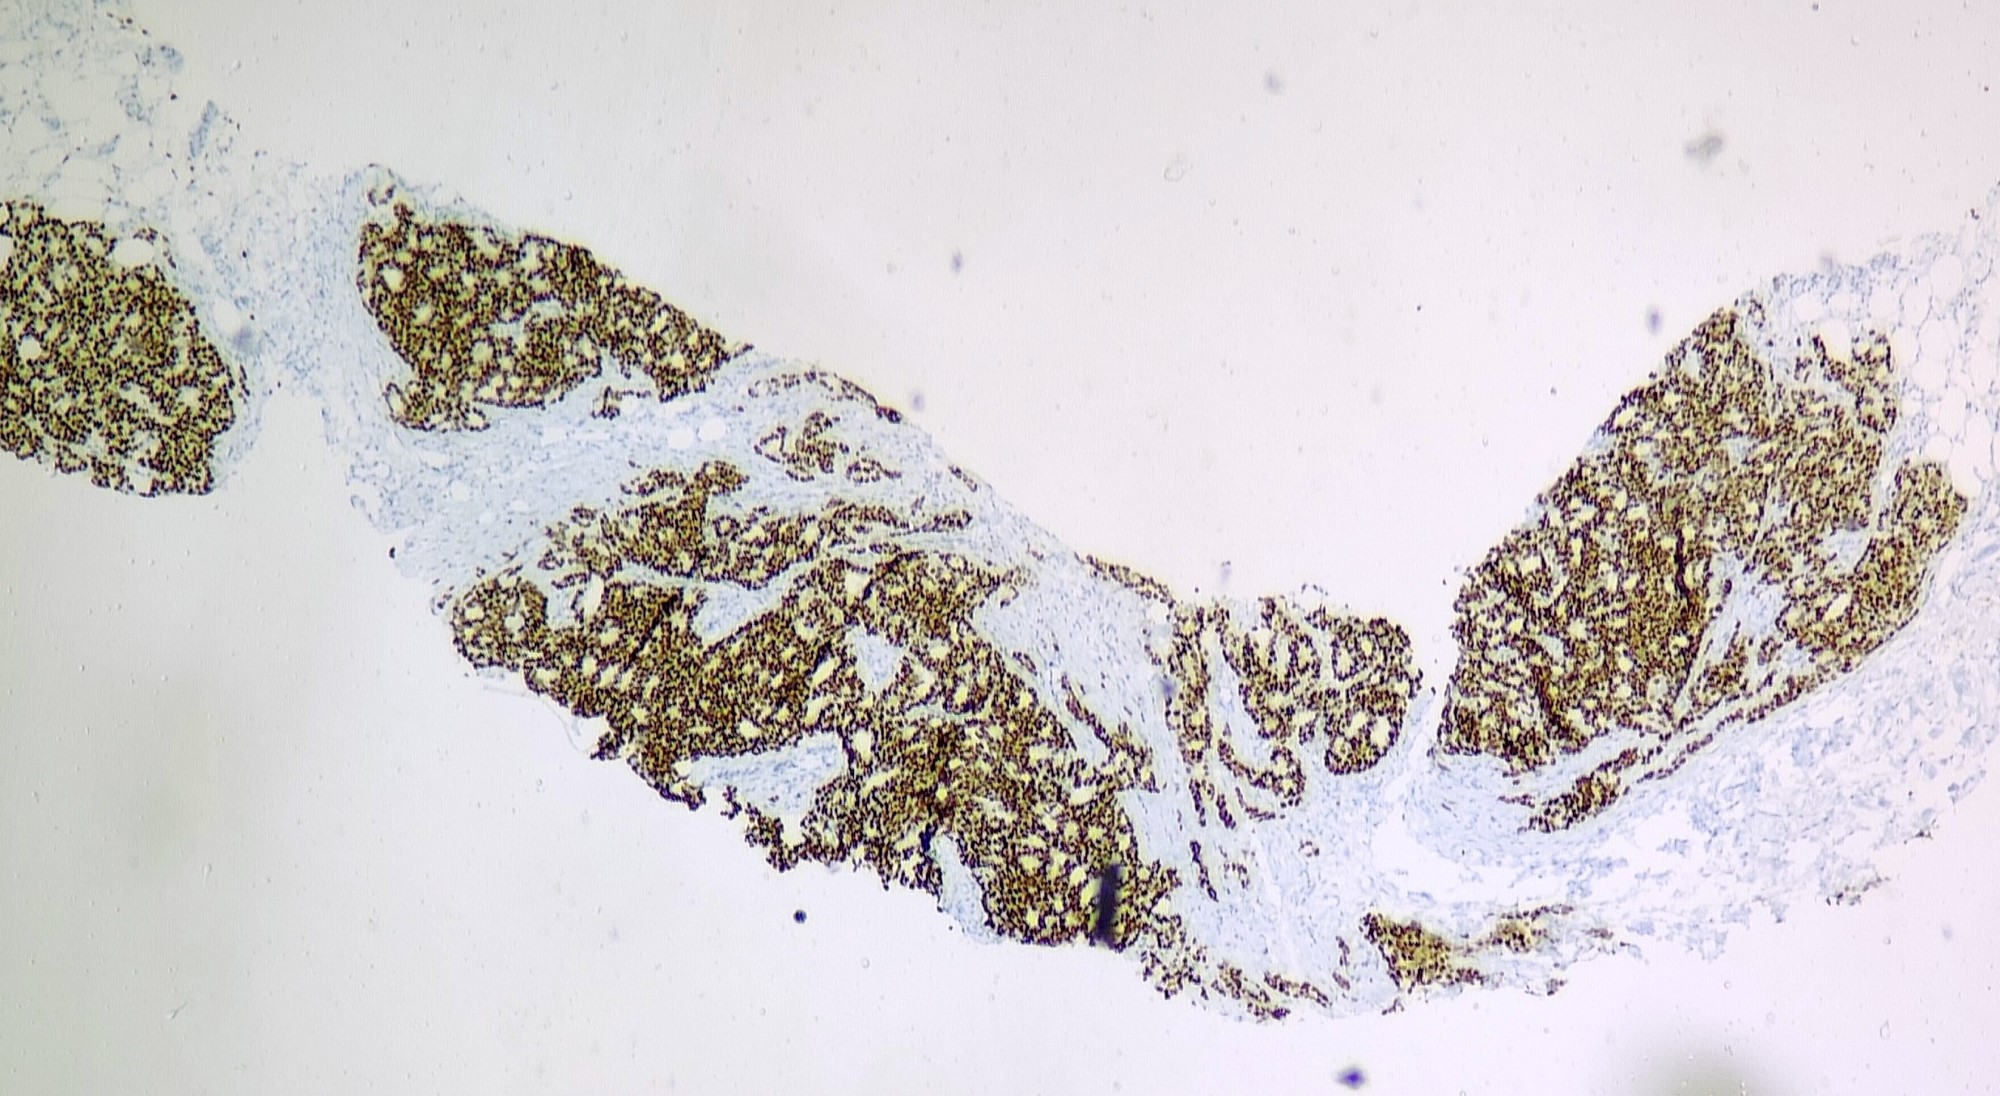

- Invasive breast carcinoma with > 90% of tumor composed of cribriform islands of malignant epithelial cells

- ER+ and HER2-

Microscopic (histologic) images

Contributed by Sunitha Shankaralingappa, M.B.B.S, M.D., D.M.

Negative stains

- HER2

- Myoepithelial markers: distinguish ICC from cribriform DCIS

- Immunohistochemical biomarker results: estrogen receptor positive (90%, strong intensity), progesterone receptor positive (50%, moderate intensity), HER2 negative (score 0).